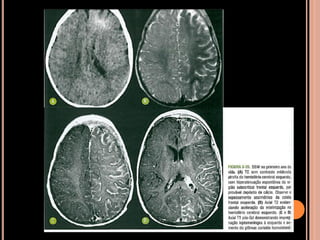

Área de vacuolização de mielina

 Origem é controversa;

 Achado típico em crianças com NF1;

 Focos hiperintensos em T2 e no FLAIR em núcleos

da base, cápsula interna, tronco encefálico e

cerebelo;

 Mais comum no globo pálido, geralmente bilateral;

NF1

Vacuolização de mielina

 Aparecimento geralmente aos 3 anos  aumenta

até os 12 anos  tendência a regredir;

 Raro observar após os 20 anos de idade;